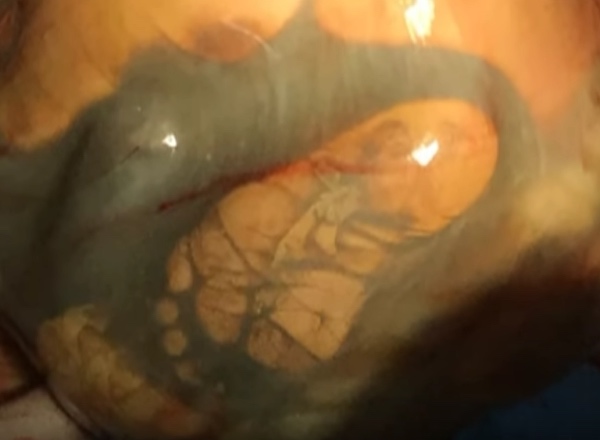

Mesmo dentro de um quadro de alto risco, o qual foram necessários 10 médicos para ajudar, Veronika veio ao mundo na 41ª semana de gestação.

“Entendemos que a cirurgia havia sido um sucesso quando a menina entregue começou a gritar. Parecia-me que não havia nada mais importante do que esse grito”, disse outro médico da equipe, Marat Zhazhiev.

Os médicos ainda estão tentando compreender exatamente qual a causa do desenvolvimento de Veronika dentro do abdômen de sua mãe.